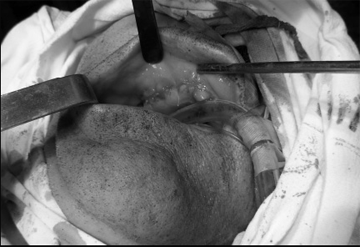

Решено произвести операцию, под общим обезболиванием: резекция области ОН верхней челюсти, ревизия верхнечелюстной пазухи справа. После обнажения кости верхней челюсти, была обнаружена четкая граница остеонекроза (рис.3). Произведена остеотомия некротизированного участка в пределах здоровых тканей (рис.4). После удаления некроти- зированного участка кости, открылось широкое сообщение с верхнечелюстной пазухой, в которой об-наружились полипозные разрастания и гной (рис.5). Были удалены патологически измененные ткани из верхнечелюстной пазухи, образовали сообщение с нижним носовым ходом, произвели тампонаду верхнечелюстной пазухи, вывели конец тампона через соустье, образованное с нижним носовым ходом. В конце, рана в полости рта была ушита наглухо (рис.6). Одновременно больному назначили антибиотики широкого спектра действия (отменили через 5 дней после операции) и местные антисептики.